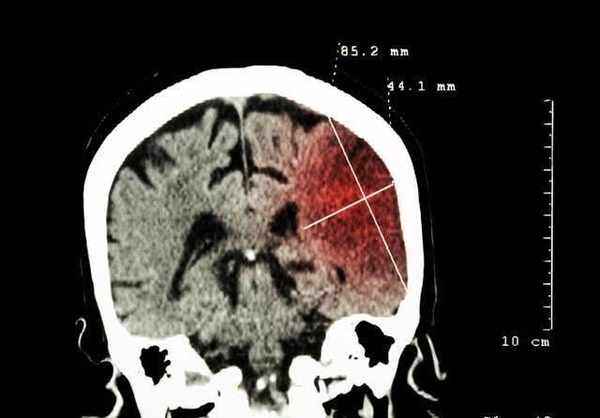

妻子看到時,立即撥打120救護車,這時已經過去很久了。醫生到達後,初步診斷是腦血管疾病。當到達醫院後,檢查了腦CT,果然如醫生所言,診斷結果為急性腦梗塞!

醫生立即進行了靜脈溶栓治療,但由於羅先生腦血管堵塞嚴重,耽擱時間過長。搶救過程中很驚險,家屬隨即接到病危通知書。

溶栓治療後約2小時,羅先生病情得到緩解,意識逐漸覺醒,四肢肌力也在慢慢恢復。病情好轉後,就被轉到住院部。

在此期間,對羅先生進行了腦血管造影,發現羅先生在腦血管已嚴重狹窄。幸好及時送到醫院,否則很可能危及生命。